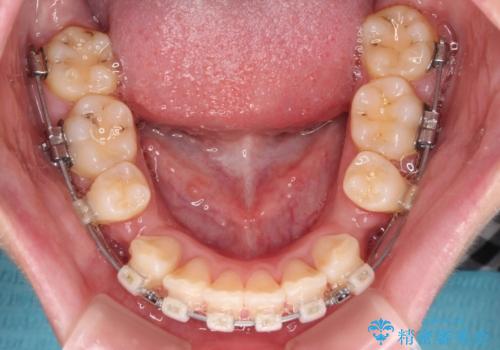

- クリアブラケット

- 前歯部のデコボコと口元が出ているのが気になるとのことで来院された患者様です。

口元の突出感の解消と、このままデコボコを解消するとさらに出っ歯傾向になってしまうことを考慮し、上下左右の小臼歯を抜歯しクリアブラケットにて矯正していくこととしました。

舌突出癖を改善するトレーニングを一生懸命やっていただいたおかげで2年以内に治療を終えることができました。